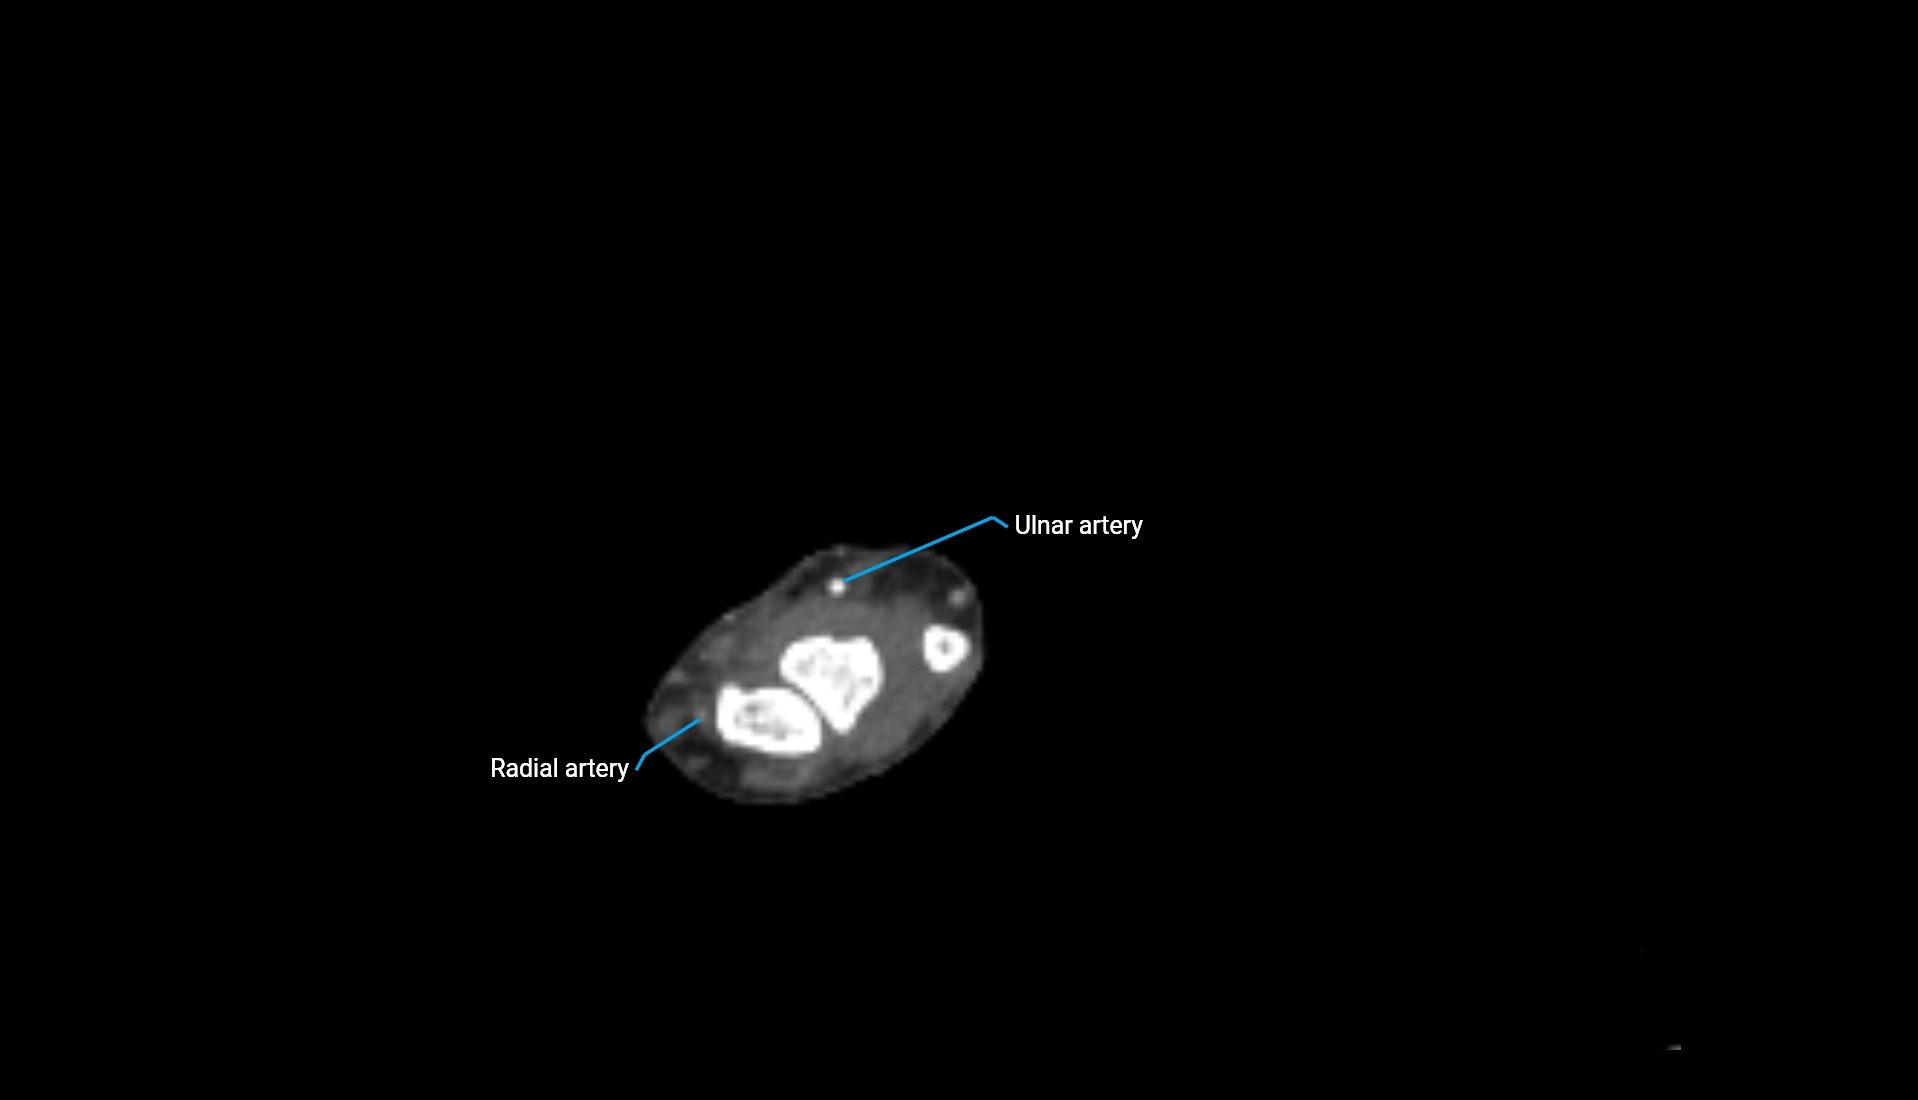

CT Appearance

Non-Contrast CT:

• Cortex: High-density, sharply defined

• Subchondral bone: Dense cancellous matrix

• Articular surface: Smooth concave contour articulating with the capitellum

• Excellent for evaluating bone integrity, alignment, and subtle fractures